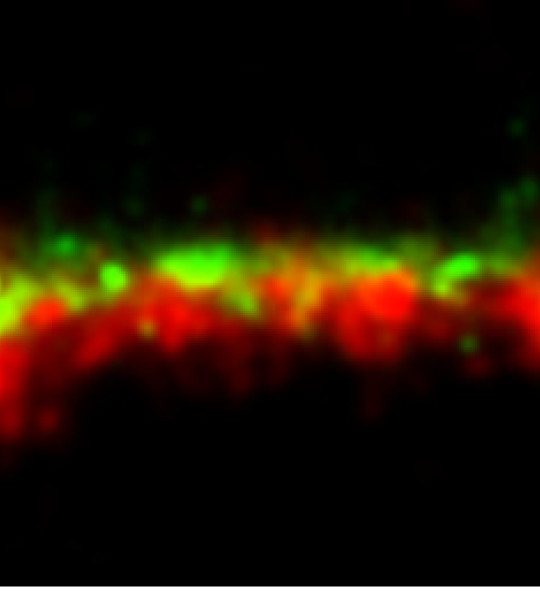

Novel imaging of kidney disease

STORM image of membranous glomerulonephritis